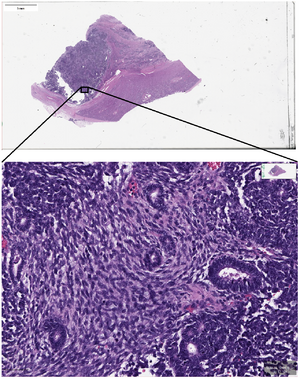

Trained pathologists traditionally view tissue slides under a microscope. These tissue slides may be stained to highlight cellular structures. When slides are digitized, they are able to be shared through tele-pathology and are numerically analyzed using computer algorithms. Algorithms can be used to automate the manual counting of structures, or for classifying the condition of tissue such as is used in grading tumors. They can additionally be used for feature detection of mitotic figures, epithelial cells, or tissue specific structures such as lung cancer nodules, glomeruli, or vessels, or estimation of molecular biomarkers such as mutated genes, tumor mutational burden, or transcriptional changes.[15][16][17] This has the potential to reduce human error and improve accuracy of diagnoses. Digital slides can be easily shared, increasing the potential for data usage in education as well as in consultations between expert pathologists. Multiplexed imaging (staining multiple markers on the same slide) allows pathologists to understand finer distribution of cell-types and their relative locations.[18] An understanding of the spatial distribution of cell-types or markers and pathways they express, can allow for prescription of targeted drugs or build combinational therapies in a personalized manner.